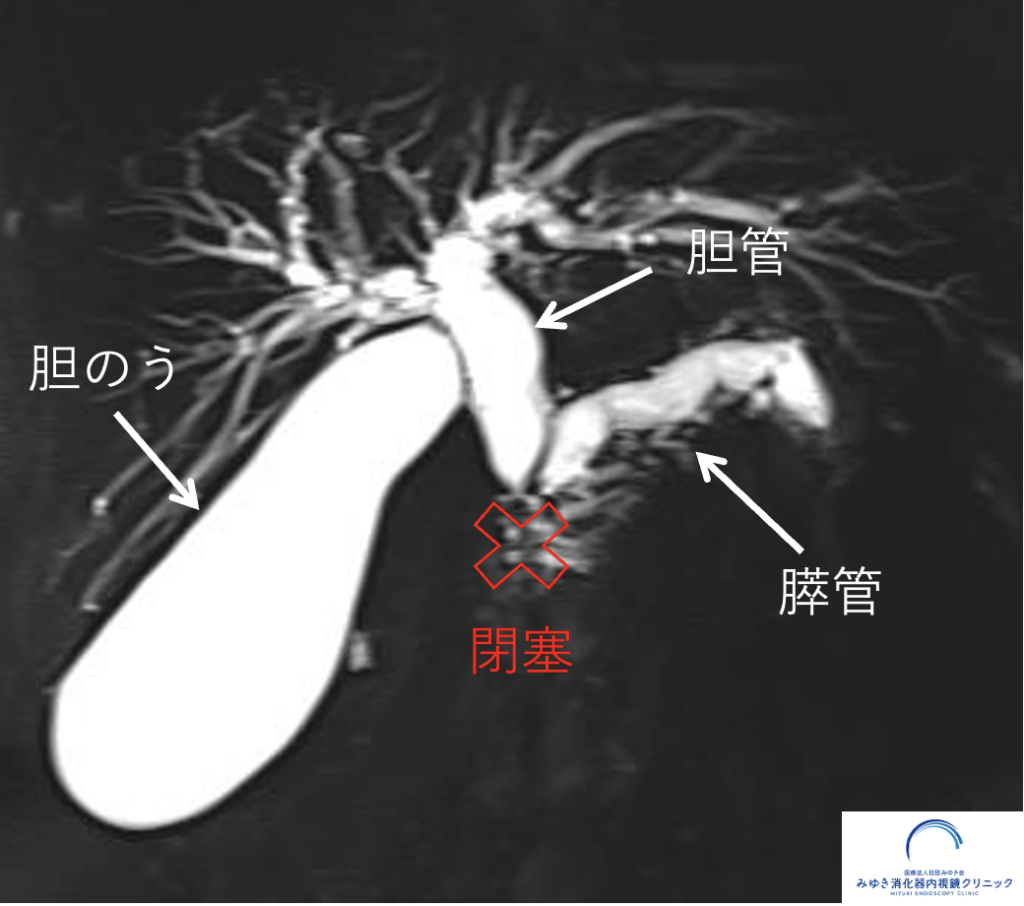

膵管拡張を指摘された場合、検査の目的は「膵管がなぜ太くなっているのか」を確認することです。 腹部エコー、CT、MRI/MRCP、超音波内視鏡(EUS)にはそれぞれ役割があります。

| MRI/MRCP | 膵管・胆管・嚢胞の全体像を把握しやすい | 小さな腫瘍の評価には限界があることがある |

膵管拡張は、単独ではすぐに膵がんを意味するものではありません。 しかし、膵管の一部が急に細くなっていたり、上流の膵管が拡張していたりする場合には、 その背景に小さな病変が隠れていることがあります。

以下は、膵管拡張をきっかけに詳しく調べたことで、 膵上皮内がん(ステージ0膵がん)の診断につながった症例です。 MRI/MRCPで膵管の変化を確認し、さらに超音波内視鏡(EUS)で詳しく評価しています。

膵管拡張からステージ0膵がんの診断につながった症例

膵管拡張をきっかけに精密検査を行い、膵上皮内がん(ステージ0膵がん)の診断につながった症例を紹介しています。